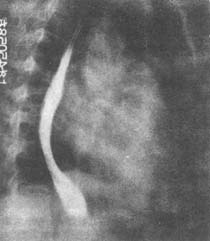

2.有佝僂病或骨軟化者可做X線照片和骨密度測量。